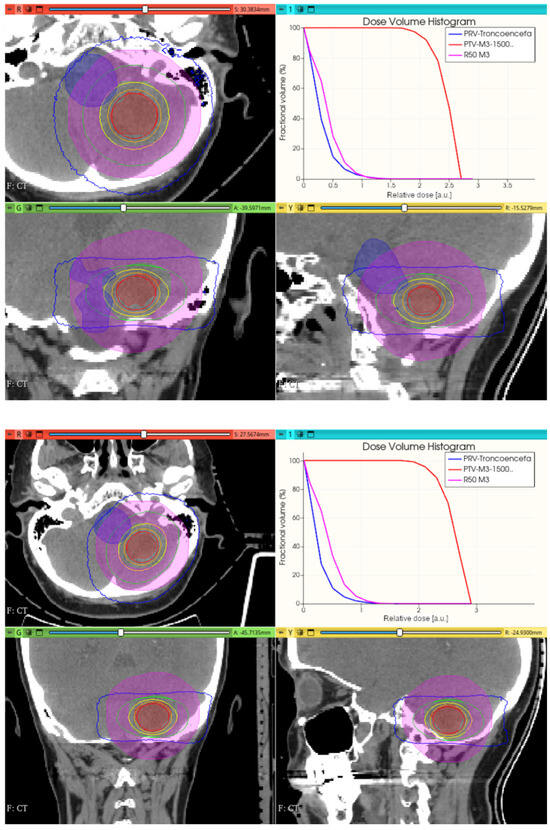

3.3.1. Preliminary CONVERAY Dosimetry Performance for Intracranial Irradiations

3.3.2. Preliminary CONVERAY Dosimetry Performance for Thoracic Irradiations